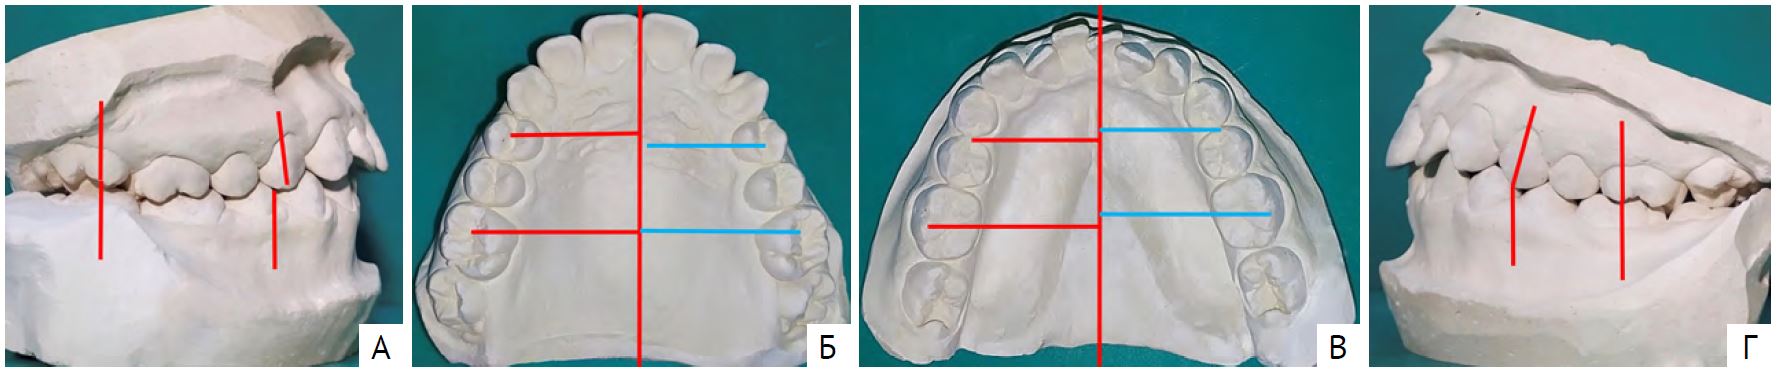

На диагностических моделях челюстей (рис. 1) изучали ширину и длину передних отделов зубных рядов по методам Pont и Korkhaus. По причине отсутствия в ряду зубов 1.2 и 2.2 сумму ширины коронок резцов верхней челюсти вычисляли по формуле с применением индекса Tonn (SI'=si×4/3). Выявили сужение зубных рядов, укорочение правого бокового сегмента и асимметрию нижнего зубного ряда.

Рис. 1. Диагностические модели челюстей пациента Л., возраст 8 лет 6 мес: А — вид справа; Б — модель верхней челюсти; В — модель нижней челюсти; Г — вид слева